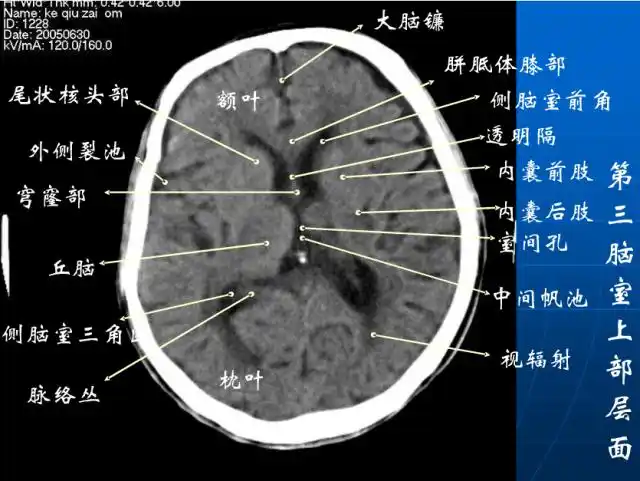

头颅ct解剖与常见出血梗死判读

头颅ct 解剖图谱,人手一份

头颅ct断层解剖